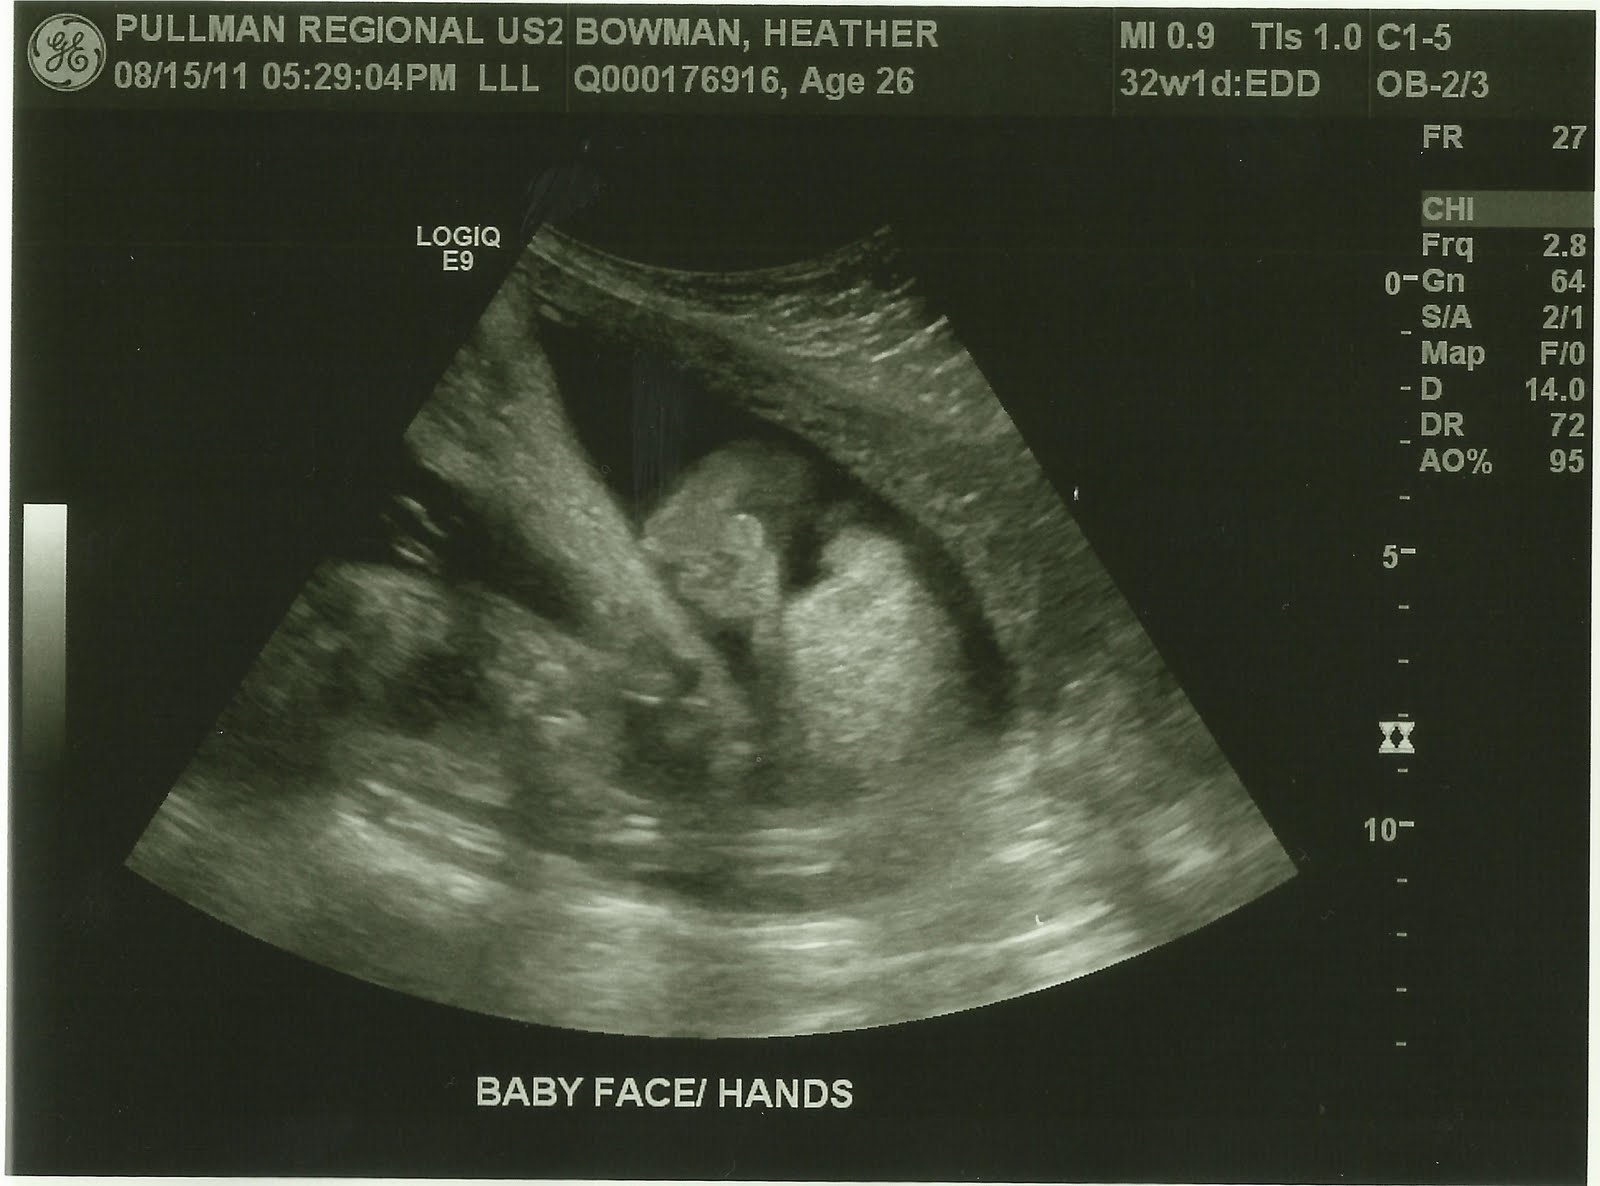

During week 33 the baby is about the size of a pineapple! It is almost 18 inches long and weighs about 5 pounds! He's getting nice and big! So far he is right on track and healthy! :) Which is always great news, especially for a diabetic!